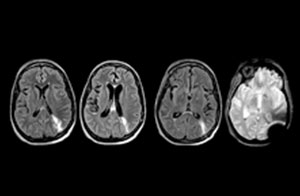

“One of the most important decisions an ED physician has to make is to admit or discharge their patient. So a physician who is better informed by an MRI exam can make this decision with more confidence. By converting to a test that has a far better potential to identify issues, physicians get a better and more certain diagnosis."

"In my experience a negative MRI, because it is so sensitive to abnormality, far exceeds the value of a negative CT. A negative MRI can allow physicians to be more confident about making discharge decisions, potentially reducing the number of admissions in cases of doubt, and offering cost savings for the institute."

“There are far more decisions being made to send people home than to admit. And in terms of making that decision, I believe there’s no more valuable exam than a negative MRI for neurologic disorders.”